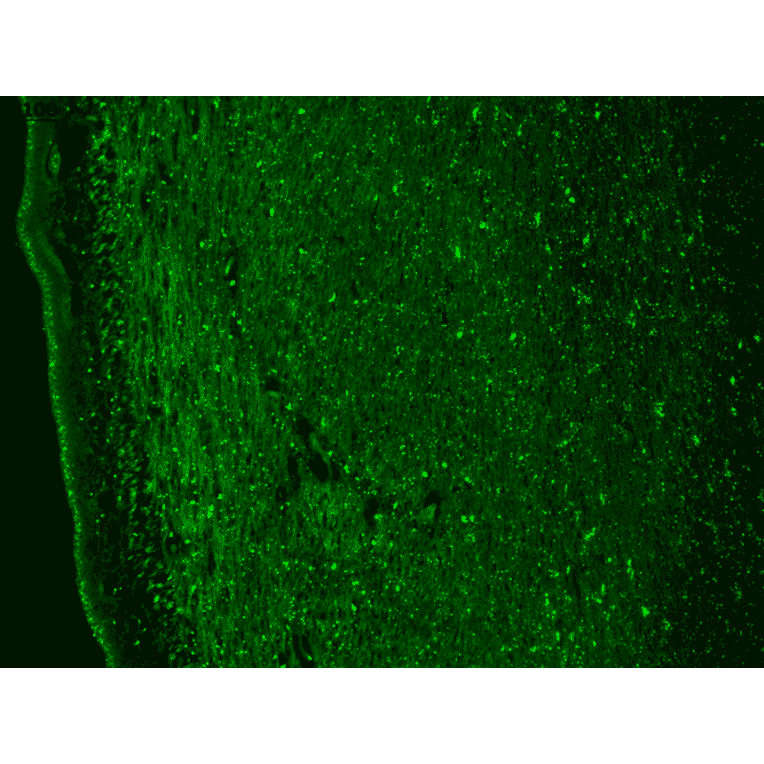

Immunohistochemistry analysis of human hippocampus, fixed in Bouin's fixative solution and paraffin-embedded. The Primary Antibody used was Anti-CACNA1H Antibody [N55/10] (A304750) at 1:1,000 for 1 hour at room temperature. The secondary antibody used was FITC Goat Anti-Mouse (green) at 1:50 for 1 hour at room temperature.